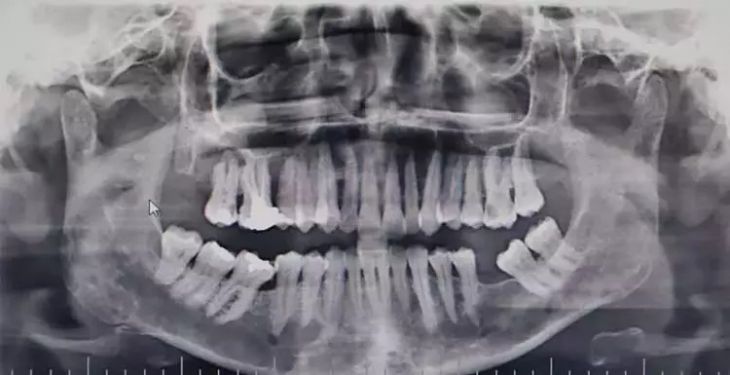

OMÜ Diş Hekimliği Fakültesi Dekanı Prof. Dr. Kaan Gündüz, vatandaşların ağız içi yaraları çoğu zaman önemsemediğini, tütün kullanımı, yetersiz ağız bakımı, güneş maruziyeti ve HPV virüsünün ağız kanserlerinin artışında etkili olduğunu ifade etti. Ağızda 2 haftadan uzun süren yaralar, sebepsiz diş sallanması, uyuşukluk ve çene ağrıları mutlaka dikkate alınması gerektiğini belirten Prof. Dr. Gündüz, ağız kanserinden korunma yolları arasında tütün ve alkol kullanımını azaltmak olduğunu belirtti. Prof. Dr. Gündüz, “Oral kanserler dediğimiz şey aslında başlangıçları çok hızlı ve sinsi gelişen durumlar. Bundan dolayı mutlaka hastaların 2 haftadan uzun süren ağızdaki yaraları eğer mevcutsa en yakın diş hekimlerine başvurmaları gerekmekte. En son yapılan, 2022 yılında Sağlık Bakanlığı yapmış oldu araştırmada 2 bin 246 tane ağız kanserine rastlanmış. Bu vakaların 551 tanesi ölümle sonuçlanmış. Bu da Türkiye kanser görülme olasılığını yüzde 1'ine tekabül ediyor ama şimdi şöyle bir durum var. Şimdi bizim insanlarımız kulağından bir damla kan gelince hemen işte gerekli doktora gider iken ağzından kan gelme durumunda çok fazla önemsemiyor. Yani ağız, dişler çok fazla önemsemiyor ne yazık ki. Ancak Özellikle son yıllarda artan tütün kullanımı ki bunun formasyonları var biliyorsunuz işte ne bileyim nargilesinden, piposundan, purosundan artmasından dolayı oral hijyenin, ağız bakımının eksikliğinden dolayı ve son yıllarda özellikle sizlerin de televizyonlarda veya işte bazı haber kanallarına duyduğunuz Human Papilloma Virüsü dediğimiz HPV'nin yaygınlaşmasından dolayı güneşe maruziyetinden dolayı insanlarda özellikle oral kanserler çok daha fazla sıklıkla görülüyor” diye konuştu.

Ağız kanserinde erken tanı gerçekleşirse hastaların ölümle sonuçlanmasının önüne geçilebileceğini ifade eden Prof. Dr. Gündüz, “Biz kurum olarak Karadeniz'in en büyük üniversitesiyiz ve de fakülte olarak da Karadeniz'de büyük bir hizmet vermekteyiz. Ortalama yaklaşık günde 500 hasta, aylıkta 10 bine yakın hasta bakıyoruz. Biz yapmış olduğumuz seminerlerde hem öğrencilerimizi hem asistanlarımızı hem de halkımızı bu konuda bilgilendirmeye çalışıyoruz. Erken tanı eğer gerçekleşirse bu hastalıkların ölümle sonuçlanmasının nispeten önüne geçmiş oluyoruz. Çünkü erken tanı biliyorsunuz her kanser vakasında çok önemli bir yer tutmakta. Herhangi birisi ağzında eğer 2 haftanın üzerine geçmeyen bir yara varsa mutlaka en yakın diş hekimine başvurması gerekmekte. Sebepsiz yere dişlerin sallanması, uyuşukluk olması, yüzde sebepsiz ağrıların, çene bölgesinde sebepsiz ağrıların oluşması kanserlerin başlangıç bulguları arasındadır. Zaten kanserlerin en fazla oluştuğu yerler ağız içerisinde dilin özellikle arka kenarlarıdır. Bunlar ne yazık ki başlangıçları da ağrısız olduğu için bir kısmının gözden kaçabilmekte. O yüzden insanlarımızdan, halkımızdan bu konuda dikkat etmeleri, eğer böyle bir lezyonla muhatap olurlarsa mesela bir yakınından ağız içerisindeki görüntüsünü çekmesini talep etmeli. 2 hafta sonra da aynı şekilde bu görüntü duruyorsa veya daha da büyümüşse en yakın merkeze gitmesini önermekteyiz” ifadelerini kullandı.